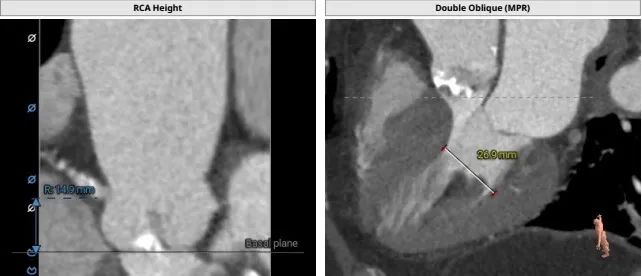

CT提示:

主动脉根部:

TYPE0型二叶瓣,瓣叶增厚,轻度钙化,左冠开口高度约11.4mm,右冠开口高度约14.9mm,法式窦结构尚可,STJ高度约20.2mm、直径约27.9mm,升主动脉增宽,最宽处约 43.6mm,心脏角度约49°,左室大小尚可,心肌增厚,工作角度:LAO22° ,CRA 30°。

入路情况:

主动脉弓部走行较平缓,可见少许钙化斑块,主动脉弓部三根毛开口未见明显狭窄征象、未见发育变异,胸主动脉、腹主动脉走行稍迂曲,可见少许钙化斑块,管腔未见明显狭窄,双侧髂动脉-股动脉走形稍迂曲,可见钙化斑块,管腔未见明显狭 窄,综合考虑,推荐右侧股动脉做为主入路。右侧股动脉穿刺水平管腔直径约为7.9mm,右侧股动脉分叉约在股骨头中下1/3水平。